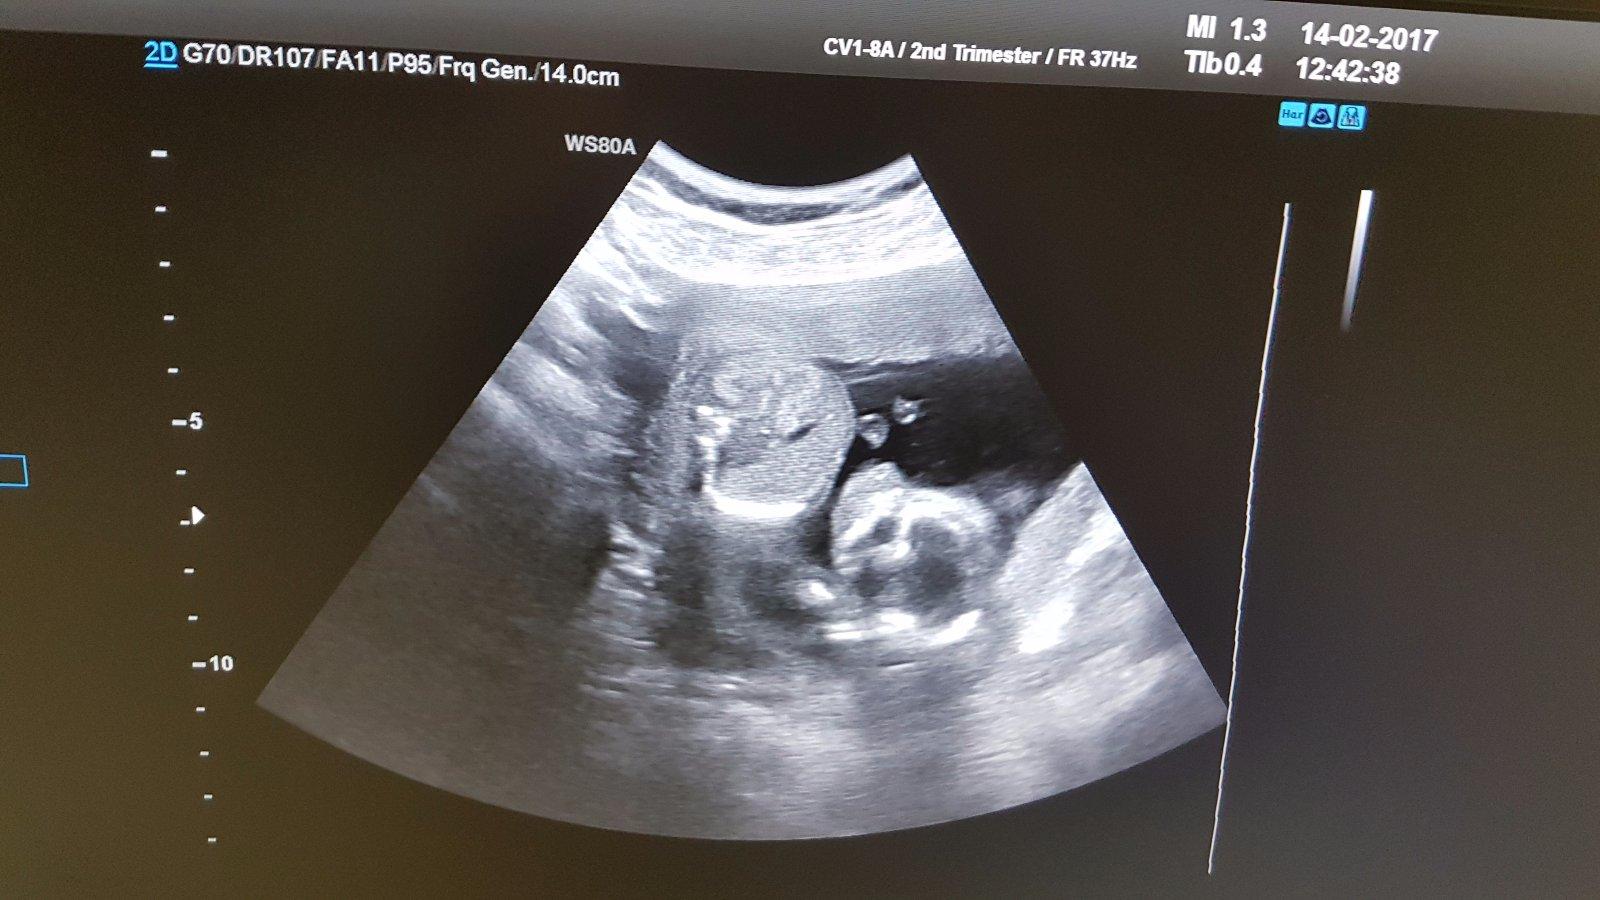

Dievcata...valentinska navsteva ambulancie prenatalnej diagnostiky dopadla vyborne...vsetko je v najlepsom poriadku..babatinko je maly neposlusnik,ktory si nechce velmi nechat nazriet do tvare ;) ale pipika nam ukazal ..takze sprava dnesneho dna: cakame syna!!! Ma cez 10 cm a vazi 143g. A je nadherny ;) podla sona zaciatok 17tt